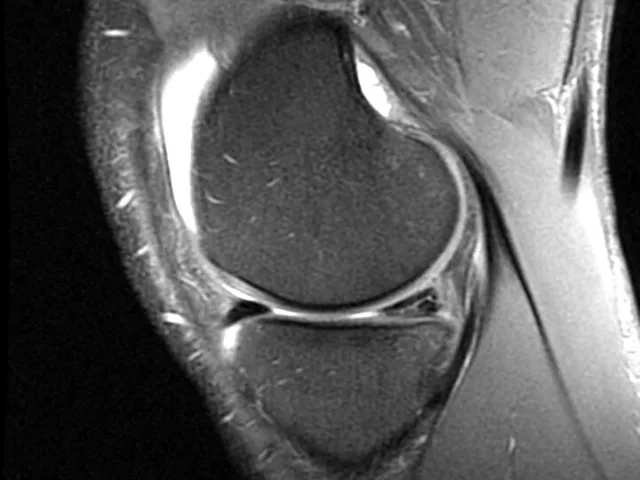

This learning module, designed for Level II radiologists, is created to help radiologists on their sub-specialization path. It is designed to demonstrate the common meniscal pathologies, common injury mechanism and associated findings. Once the module is completed, the trainee should be able to correctly describe a meniscal tear and to assess its stability.

- To know and correctly describe a meniscal tear

- To be able to recognize indirect signs

- To learn how to assess the stability of a meniscal tear

- To become familiar with a common injury mechanism involving the menisci